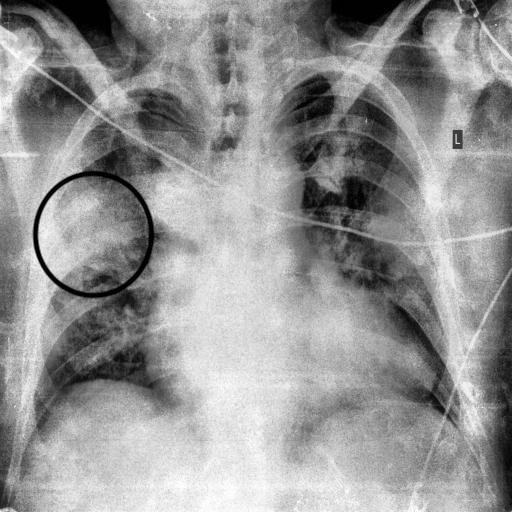

In this work, we only consider the CXR images in a frontal view, namely Poster anterior (PA) and Erect anteroposterior (AP). The first two databases in the above list comprise 520 such images. For the training purpose, we have used these images along with 520 CXR images of normal and pneumonia cases from COVID-19 Radiography Database (Kaggle) COVID19R73:online and Mendeley Chest X-ray Images kermany2018large . Figures 1(a) and 1(b) depicts the manually marked region of interest that distinguishes between COVID-19 and Pneumonia cases in CXR images. The above regions are marked by a radiologist after clinical evaluation of these CXR images.

Figure 8 (a)-(c) shows images relating to COVID-19, Pneumonia, normal cases, respectively. Each subfigure in a row comprises three images of the same patient relating to a medical condition. In each row, the clinical condition has been marked by a radiologist in the first image. In the second image in the same row, the top 10 superpixels obtained using LIME have been marked using green and red colors. Superpixels contributing toward and against the predicted class appear in green and red colors, respectively. Finally, the third image in the same row depicts the LIME-generated heatmap corresponding to the second image. The intensity of the blue color of a particular region in the heatmap corresponds to its relative significance in predicting its class. A radiologist confirmed that in the case of Anteroposterior (AP) chest radiograph (Figure 8(a)), the ill-defined area of ground glass haze in the right lung parenchyma at mid-zone likely represents COVID-19. Similarly, in the Anteroposterior (AP) chest radiograph (Figure 8(b)), the wedge-shaped area of consolidation in the right lung parenchyma at the upper zone likely represents pneumonia. The radiologist confirmed that the regions (though not all) highlighted by LIME correspond to the affected regions in case of both COVID-19 and Pneumonia. This points to the applicability of COV-ELM in the identification of medical conditions such as pneumonia and COVID-19.